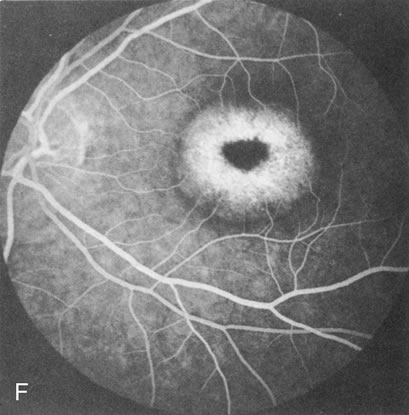

Fluorescein angiography highlights observable fundus findings. In patients with a golden reflex the FA is normal (Fig. 2E, F) or shows a mild transmission hyperfluorescence.7